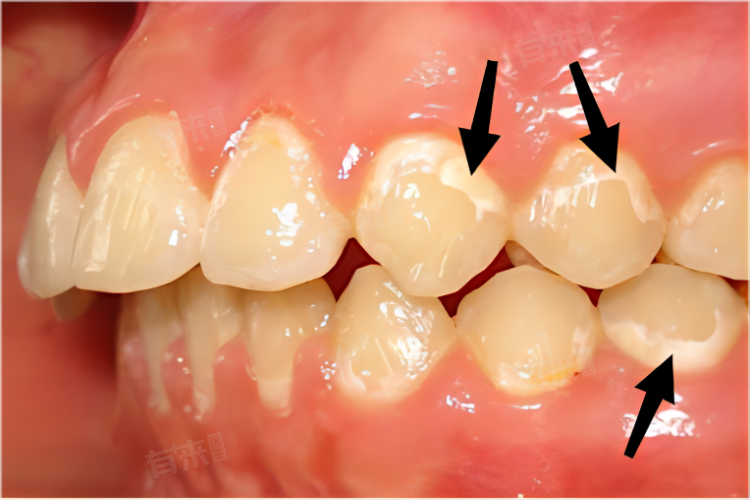

- 对于钙化较严重的牙齿,如已形成明显白斑或斑点,建议患者及时就医,接受专业口腔治疗,医生可能会根据具体情况,采用氟化物治疗、微研磨术或渗透树脂修复等方法,以改善牙齿的外观和功能。